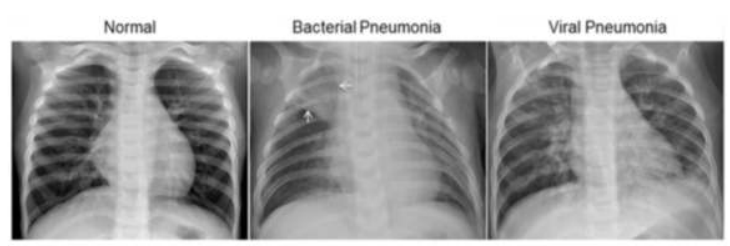

1) Chest X-ray

X-ray 검사를 통해 폐렴을 대엽성 폐렴, 기관지 폐렴, 소엽성 폐렴, 간질성 폐렴으로 분류할 수 있다.

세균성, 지역사회 획득 폐렴은 하나의 폐 분절엽(lung segmental lobe)의 페경화(lung consolidation)를 나타내지만, 결과는 다를 수 있으며 다른 유형의 폐렴에서는 다른 패턴이 일반적이다.

바이러스성 폐렴 (Viral pneumonia) :

정상으로 보이거나, 과팽창되거나, 양측 반점 부위가 있거나, lobar consolidation(대엽 경화)을 동반한 세균성 폐렴과 유사하게 나타날 수 있다.